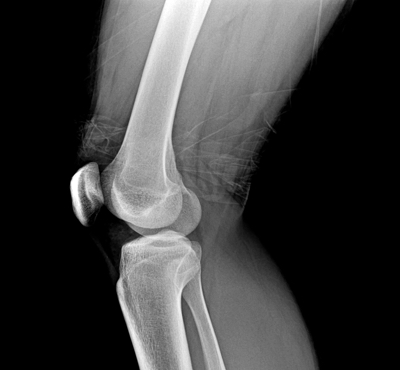

In animal studies TG-C has shown to be effective in treating Rheumatoid Arthritis (RA). RA is an autoimmune disorder in which the individual's own immune cells attack the joints resulting in inflammation and damage to the articular cartilage and bone matrix. RA commonly occurs in the fingers and wrist, and is particularly observed in the knuckles which become swollen. Unlike OA which occurs in elderly populations, RA is often observed in young adults. The differences between OA and RA are shown in the table below.

When TG-C was injected into a rheumatoid arthritis (RA) animal model of inflammation, preliminary results in reducing the inflammatory response were quite promising. These results indicate the possibility of using TG-C in the future as a treatment for RA.